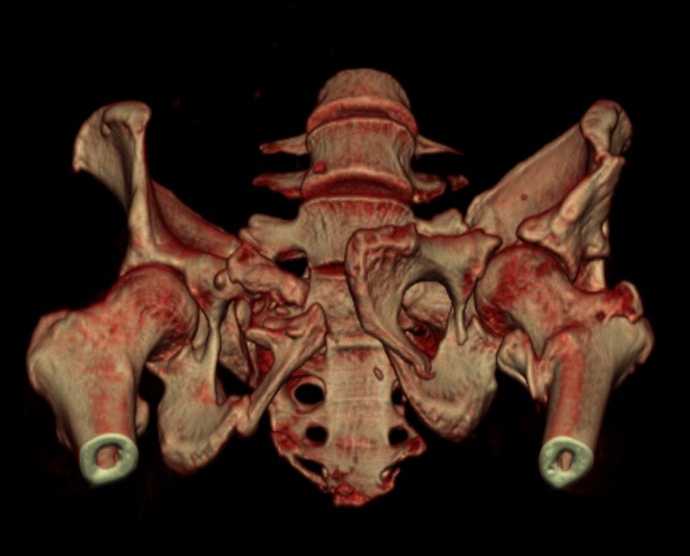

Больная 43 года (промышленный альпинист), 28.07.08 в результате падения с 5 этажа получила политравму: Перелом свода и основания черепа. Вертикально-нестабильное повреждение таза, осложнённое разрывом мочевого пузыря. Чрезвертельный перелом левого бедра. Перелом правой таранной кости, переломовывих правой кубовидной кости. Тупая травма живота, разрыв печени, ушиб почек. Забрюшинная гематома. В день травмы - лапаротомия, ушивание ран печени. Разрыв мочевого пузыря не диагностирован. Течение болезни осложнилось развитием мочевого затёка и обширной пред- и забрюшинной флегмоны, сформировался свищ мочевого пузыря. 19.8.2008 вскрытие, дренировние флегмоны, ревизия мочевого пузыря, обтурация мочевого свища (свищ закрылся в октябре), 1.10.2008 некрэктомия, пластика по Шеде-Лидскому правой кубовидной кости. По результатам КТ диагностирован рак правой почки (диагностическая находка), 8.10.2008 нефрэктомия справа. Переломы велись консервативно. Имеется вертикальное смещение левой половины таза с выраженным отведением крыла (клинически подвижности нет), несросшийся низкий двухколонный перелом левой вертлужной впадины с потерей конгруэнтности, укорочение около5 см, застарелый разрыв лонного сочленения, неправильно сросшиеся переломы обеих ветвей правой лонной кости с укорочением, патологическая подвижность лоно-седалищного фрагмента слева. Правая нижняя конечность неопорна, несмотря на то, что лежа прямую ногу поднимает, ходит на левой ноге (ортопедическая обувь) с костылями, справа тазобедренный ортез. Седалищные нервы работают.Урологи отпустили больную на 6 мес.